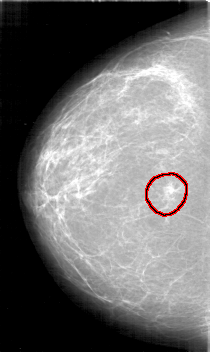

D_4126_1.RIGHT_CC

RIGHT_CC LINES 5266 PIXELS_PER_LINE 3136 BITS_PER_PIXEL 12 RESOLUTION 43.5 OVERLAY

FILE: D_4126_1.RIGHT_CC.OVERLAY

TOTAL_ABNORMALITIES 1

ABNORMALITY 1

LESION_TYPE MASS SHAPE IRREGULAR MARGINS SPICULATED

ASSESSMENT 3

SUBTLETY 4

PATHOLOGY MALIGNANT

TOTAL_OUTLINES 1

BOUNDARY